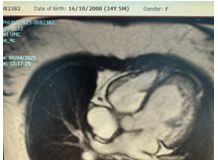

Bệnh cơ tim thể xốp với biểu hiện suy tim ở...

Bệnh cơ tim thể xốp là một rối loạn cơ tim hiếm gặp, đặc trưng bởi sự hình thành mô cơ tim bất thường, thường ảnh hưởng đến tâm thất trái, trong đó cơ tim hai...